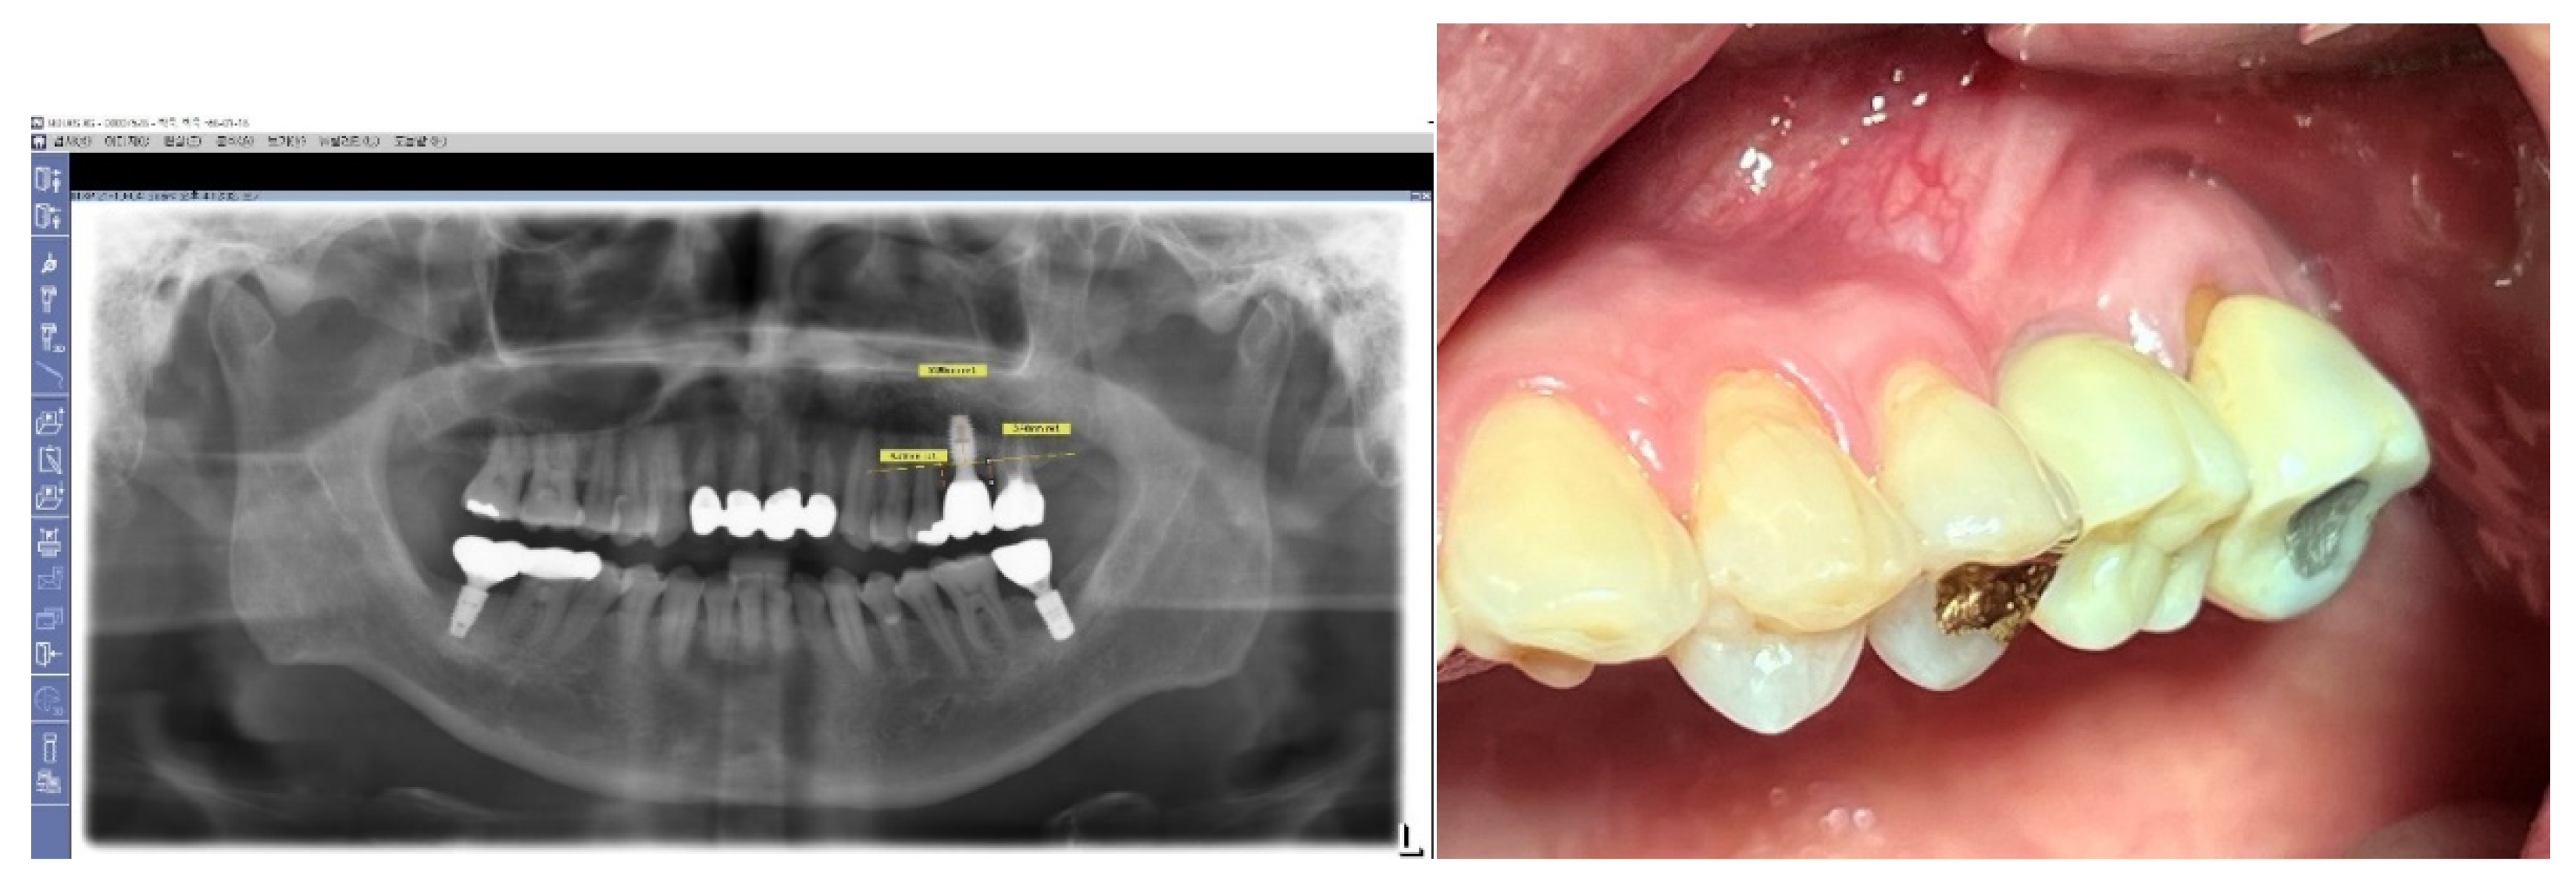

Figure 7. Long-Term Stability of Lower First Implants. This figure displays a panoramic view X-ray taken in 2023, showing the stable results of both lower first implants that were placed in 2012. These implants, which utilize Subcrestally Placed Implants (SPI) with Internal Platform Switching (IPS) design (specifically Bicon implants), demonstrate long-term stability and successful integration.

Figure 22. Natural-Looking Results Achieved by SPI Technique. This figure illustrates the effectiveness of the Subcrestally Placed Implants (SPI) technique in achieving results that closely mimic natural teeth. It demonstrates how the biologic width—comprising the transitional zone and subcrestal zone connective tissue—differs from that of natural teeth.